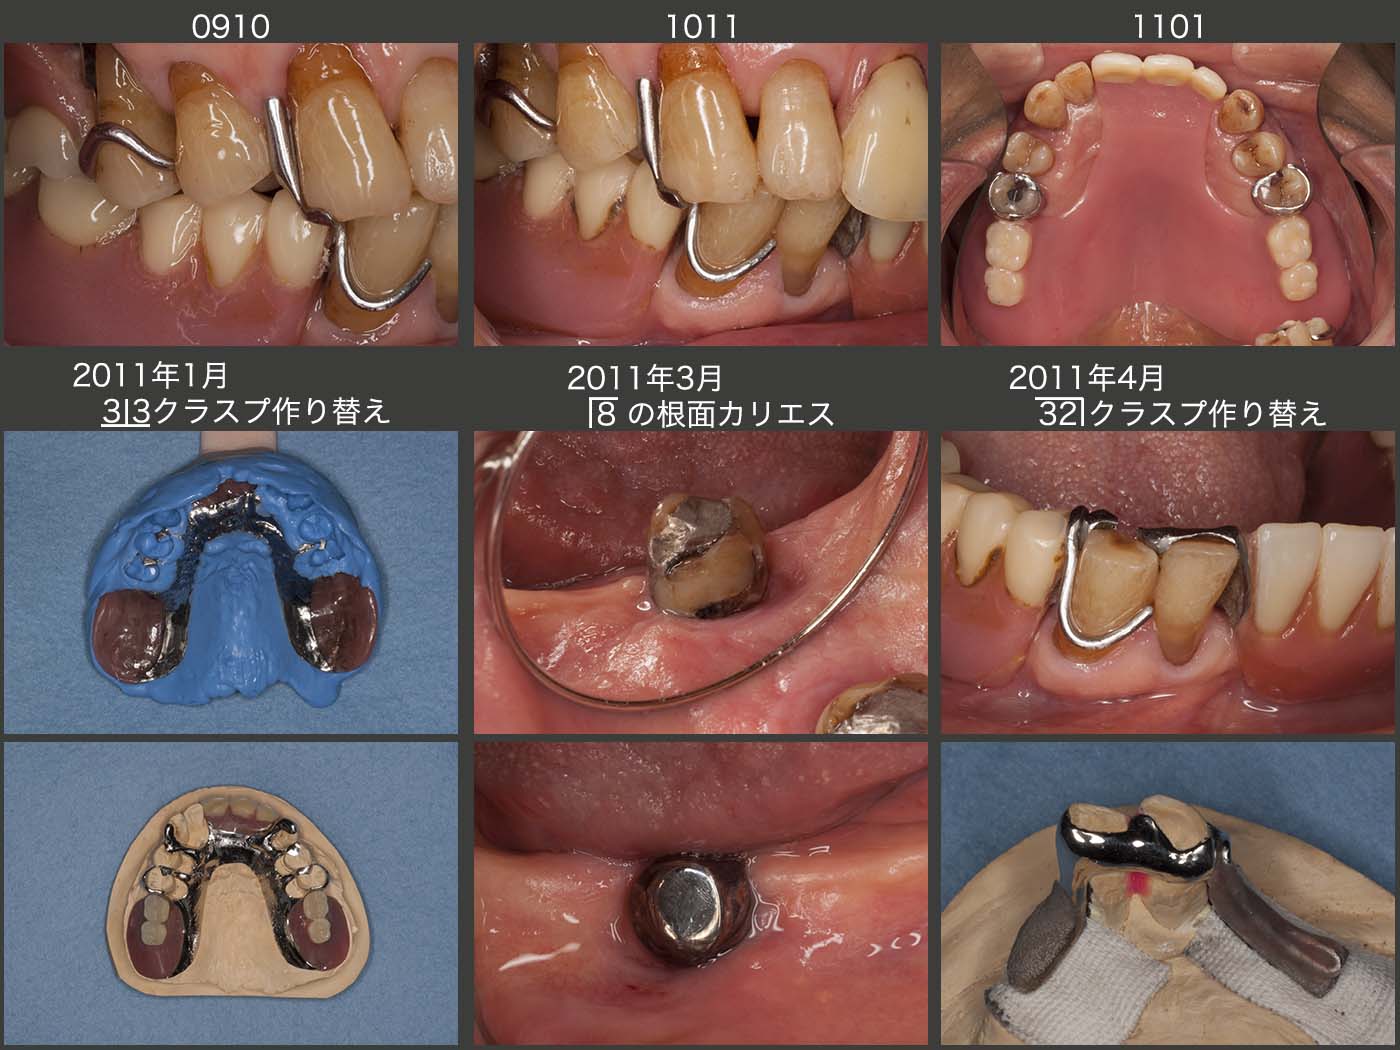

その後の経過であるが,2010年10月,初診終了後21年4ヶ月の経過観察の時,これまでまったく問題がみられなかった上顎義歯にシーソー運動が認められた.よく観察すると,スライド上段左に示す09年10月と比べて,上段中央に示す10年11月のクラスプのレストの適合が悪くなっていた.なお,この原因は上顎両側犬歯が何らかの理由で挻出したからではないかと考えている.当時は,レーザー溶接機が当院になかったので,金属床を修理するとなると外注せざるを得なかった.そうなると日数がかかるため,まず簡単な暫間義歯を製作した.(スライド上段右)つぎに,上顎両側犬歯のクラスプを除去し,同部の印象を採得したが,その状態が中段左の写真である.義歯床,犬歯以外のレストの適合は問題ないことから,やはり犬歯のクラスプが定位置に収まらない,すなわち歯の移動が生じたのではないかと思われる.

11年3月,左下8の舌側に根面カリエスがみつかった.もう一度,リングクラスプをかけるとなると同部の清掃性の改善は期待できないので,金銀パラジウム合金を用いたコーヌス冠に支台装置を変更した.ここでは,2次固定を目的とはせず,単に清掃性を重視したことによる.

11年4月,右下2,3の支台装置の適合も悪くなってきたので,再製作した.今度は当然,切端を覆うことはない.